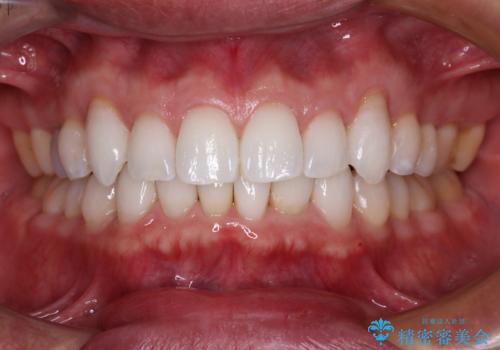

- 小さいころからの歯の変色と矯正治療の後戻りを気にして来院された患者様です。

気になる変色歯を仮歯に変え、その後歯列不正を矯正治療で改善し、最後にオールセラミッククラウンにて補綴治療することとしました。

数十年に及んだ歯の変色が改善されたため、大変満足していただきました。